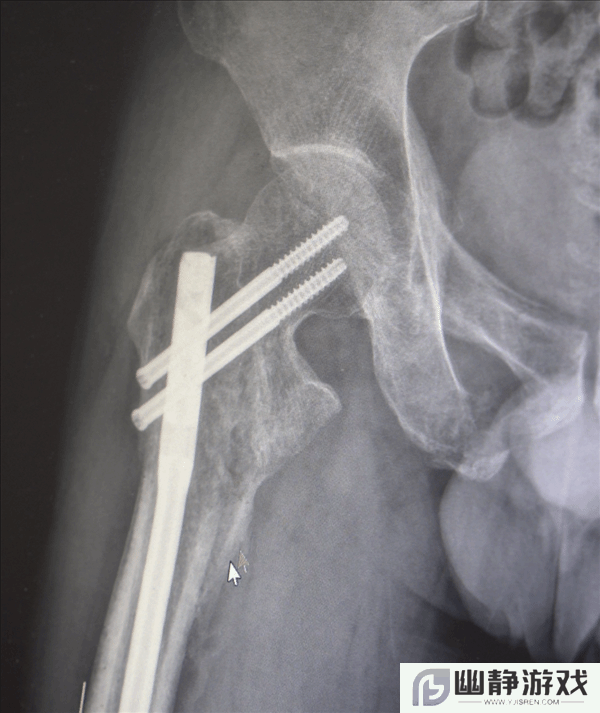

创伤性失血性休克、多发性肋骨骨折、肺部损伤、右侧肩胛骨粉碎骨折、右侧肱骨髁上开放粉碎性骨折、右股骨粗隆及股骨干粉碎性骨折、骨盆粉碎性骨折、腰椎横突多发骨折、腰骶柱神经损伤、臂丛神经损伤、胸腔积液、腹腔积液等。

经医生检查,张先生全身共有六处较大骨折部位,多为严重粉碎性骨折,全身骨折碎块达30多块!